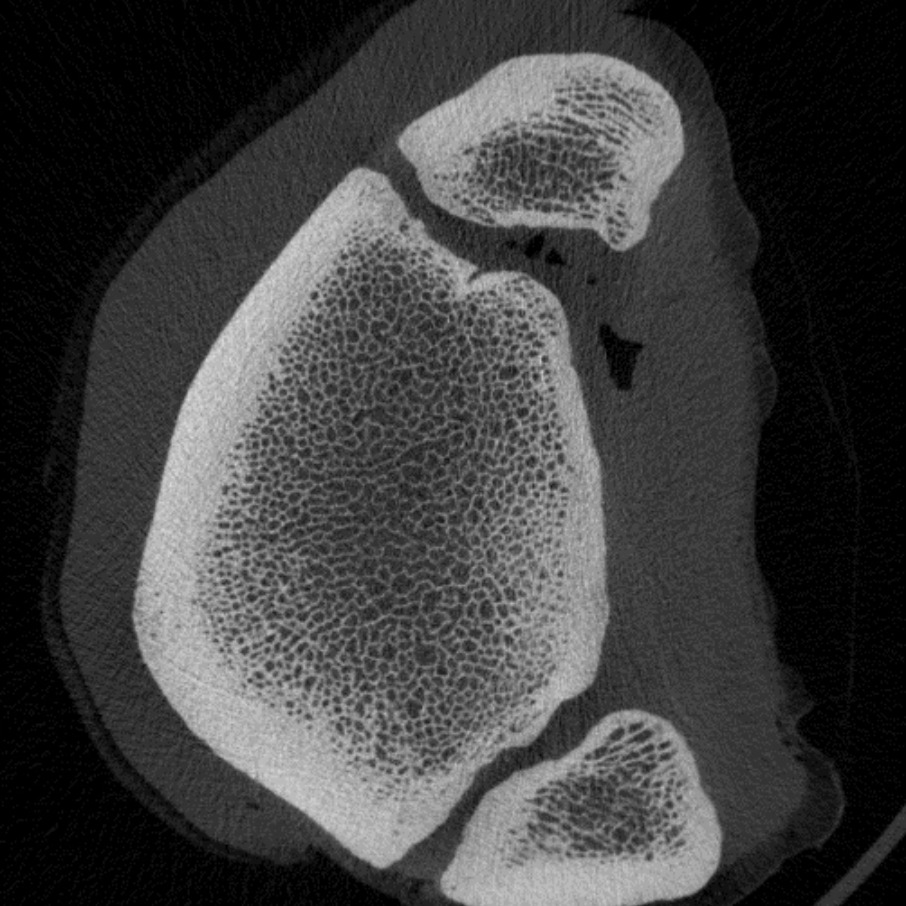

| 分辨率 | <59 µm(10% MTF) 17 µm - 273 µm标称各向同性(像素尺寸) |

| 图像矩阵 | 512 × 512 - 8192 × 8192 像素 |